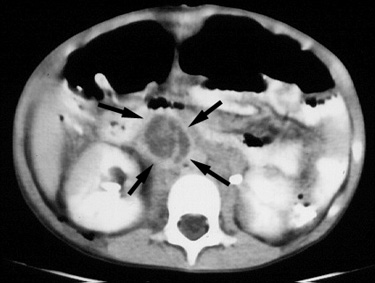

| Burkitt lymphoma mimicking appendicitis. 4 year old boy with a six week history of pain and tenderness in the right lower quadrant accompanied by fever. A CT examination was performed to evaluate for appendicitis, shown below. |

Figure 1. Contrast enhanced CT image through the lower abdomen demonstrates a low density paracecal mass (arrows). C = cecum. |

Figure 2. CT image slightly superior in location to Figure 1 demonstrates another, separate mass (arrows), anterior to the inferior vena cava, with an enhancing rim and low attenuation central portion, resembling a mesenteric abscess. |

| Biopsy revealed Burkitt lymphoma. The patient was treated with chemotherapy, resulting in regression of the tumor. |